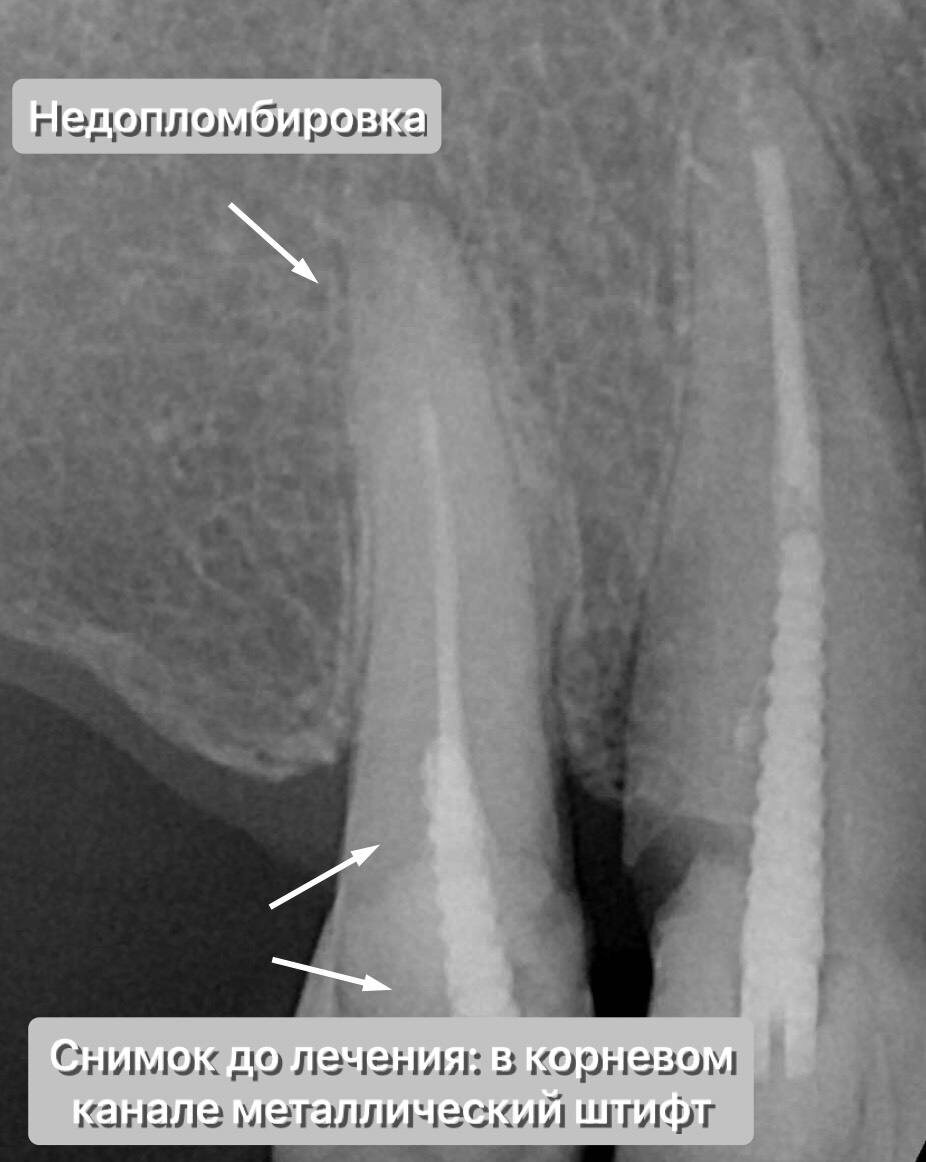

Всё как мы любим - зуб наполовину состоит из огромной дефектной пломбы, собственных стенок почти нет, кариес. Верхушка айсберга, самое интересное поджидало нас "на глубине, под толщей тёмной воды".

Но даже это мелочи - на Rg в канале различим металлический штифт, сам канал недопломбирован, визуализируется очаг деструкции на верхушке корня (периодонтит).